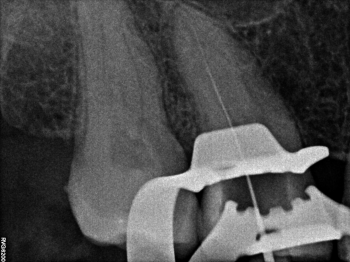

Лечение зубов под микроскопом;

Перелечивание и спасение зуба с воспалением на верхушке корня;

Прохождение корневых каналов со сложной анатомией, извлечение сломанных инструментов;

Микрохирургическое ретроградное пломбирование.